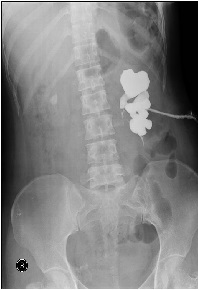

Emphysematous Pyelonephritis and Obstructive Uropathy: Case Report